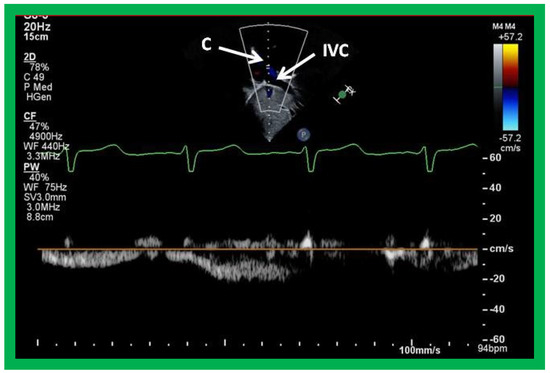

Cross-sectional views of the Fontan conduit were shown in Figure 38, Figure 39 and Figure 40. Imaging of the conduit longitudinally is also possible (Figure 46) and laminar flow in the conduit (Figure 46B) is indicative of a nonobstructive conduit. The connection between the IVC and the conduit (Figure 47 and Figure 48) can also be demonstrated by echo studies. Doppler interrogation demonstrating low flow velocities across this region (Figure 49) is indicative of nonobstructive IVC–conduit junction. Turbulent flow and high Doppler velocity across this region suggest obstruction; however, this is rarely seen.

Article Metrics

Back to TopTop